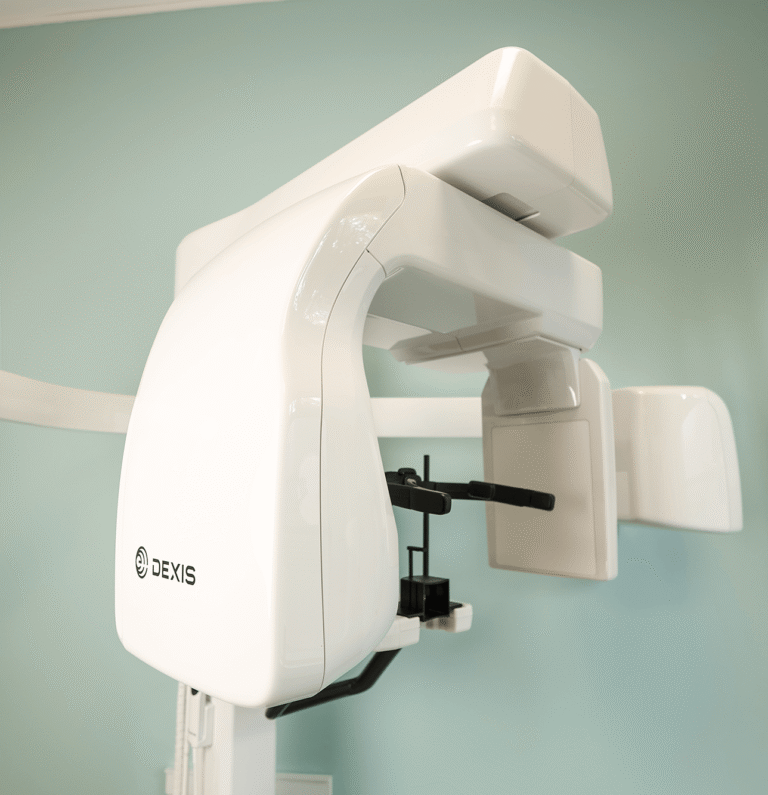

Wierzymy, że skuteczne leczenie zaczyna się tam, gdzie kończy się domniemanie, a zaczyna precyzyjna diagnostyka. Dlatego zainwestowaliśmy w zaplecze techniczne, które pozwala nam na pełny wgląd w stan zdrowia pacjenta już podczas pierwszej wizyty.

W codziennej pracy wykorzystujemy